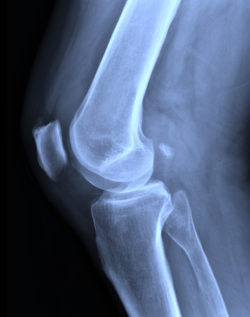

There are two major complications commonly reported with the Zimmer tibial plate that led to the March 2015 recall. The first of these problems is what is known as radiolucent lines. Radiolucent lines are visible under X-rays, and appear as gaps between the knee implant device and the bone, signifying that the device has become poorly seated. This can lead to constant pain and other problems.

The other major complications reported is device loosening, which can lead to failure of the device and even necessitate revision surgery. If a patient’s knee implant becomes loose, it can create gaps between the device and the bone—gaps large enough that they are visible in X-rays.